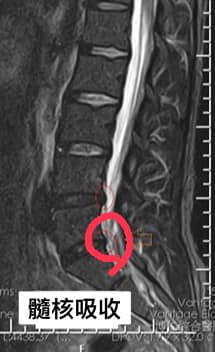

一年後,這次因為另外一條腿也有一點酸麻,有前車之鑒就趕快回門診治療,原本以為是之前的舊傷又復發,再拍攝一次MRI,沒想到意外發現原本L5/S1突出髓核已經吸收回去。